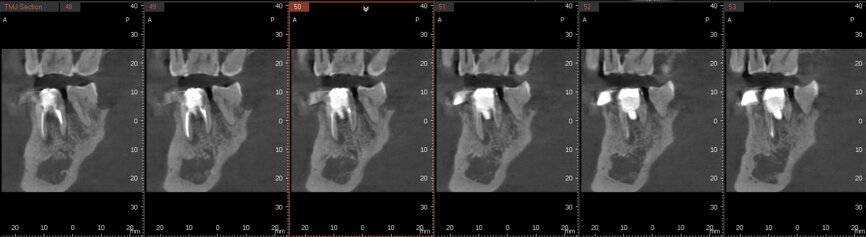

Fig. 6a: Post-op CBCT images of tooth #46 showing adequately obturated canals at all levels to the working length and sealing of the furcation defect.

Fig. 6b: Post-op CBCT images of tooth #46 showing adequately obturated canals at all levels to the working length and sealing of the furcation defect.

Fig. 6c: Post-op CBCT images of tooth #46 showing adequately obturated canals at all levels to the working length and sealing of the furcation defect.

Fig. 6d: Post-op CBCT images of tooth #46 showing adequately obturated canals at all levels to the working length and sealing of the furcation defect.

Fig. 6e: Post-op CBCT images of tooth #46 showing adequately obturated canals at all levels to the working length and sealing of the furcation defect.

Fig. 6f: Post-op CBCT images of tooth #46 showing adequately obturated canals at all levels to the working length and sealing of the furcation defect.

Fig. 6g: Post-op CBCT images of tooth #46 showing adequately obturated canals at all levels to the working length and sealing of the furcation defect.

At the next appointment, the temporary restoration was removed, and the hardness of the MTA was checked. The margins of the defect were also closely checked under the dental operating microscope to rule out any leakage. Finally, a thin layer of light-polymerising glass ionomer cement liner was placed over the MTA. Etching and bonding followed, and the core was placed using a bulk fill composite in a SonicFill handpiece (KaVo Kerr, Figs. 6a–g).